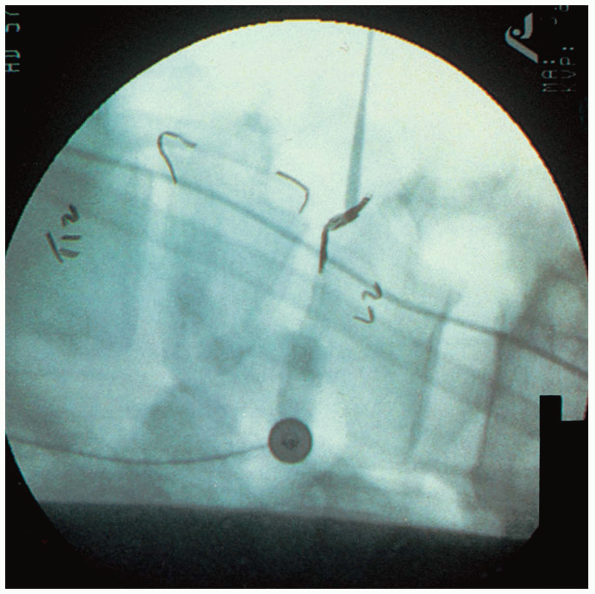

Intraoperative fluoroscopy or radiographs

of cases. The intraoperative radiograph may then be obtained (Fig. 14-20). -